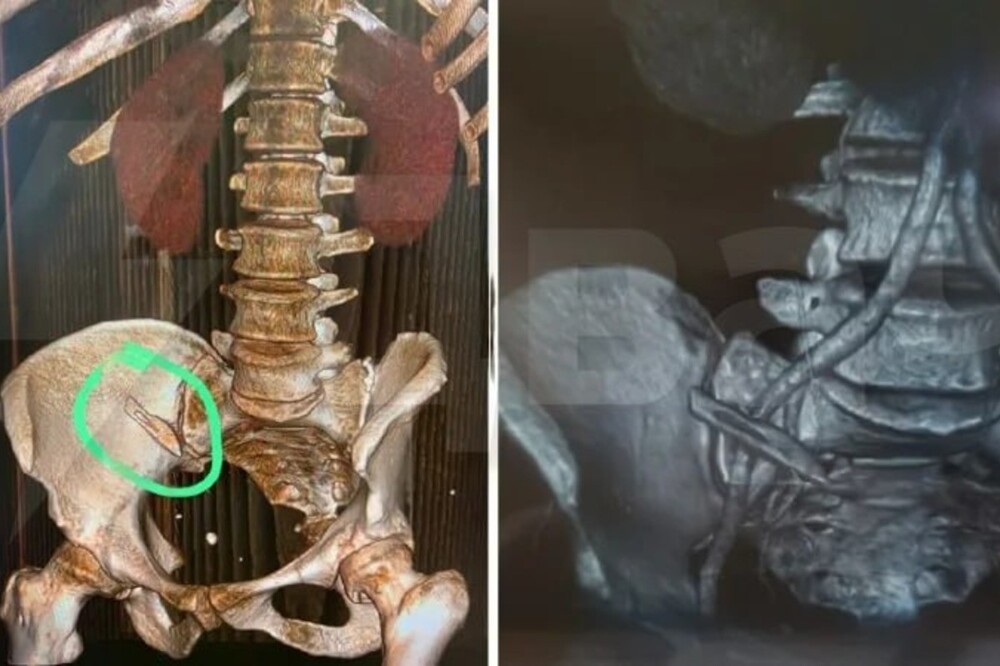

Surgeons from Sochi forgot a scalpel in the patient's body, which was found a few months later (2 photos)

Doctors from the department of purulent surgery of the hospital in Sochi operated on a woman with cancer, even in the winter. And after a few months, a scalpel was found on x-rays. Then the patient flew to Yekaterinburg to undergo chemotherapy, before which the x-ray was taken.

Doctors admitted their mistake and a foreign body from the intestine extracted. But now the victim demands for these negligent doctors punishment, and has already written a statement to the Investigative Committee. Woman also wants to achieve a fair reprimand for those doctors who examined her neoplasm during regular examinations, and because the tumor was already large.